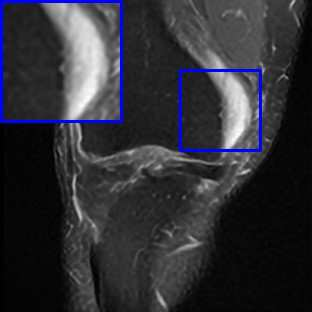

Limited by imaging systems, the reconstruction of Magnetic Resonance Imaging (MRI) images from partial measurement is essential to medical imaging research. Benefiting from the diverse and complementary information of multi-contrast MR images in different imaging modalities, multi-contrast Super-Resolution (SR) reconstruction is promising to yield SR images with higher quality. In the medical scenario, to fully visualize the lesion, radiologists are accustomed to zooming the MR images at arbitrary scales rather than using a fixed scale, as used by most MRI SR methods. In addition, existing multi-contrast MRI SR methods often require a fixed resolution for the reference image, which makes acquiring reference images difficult and imposes limitations on arbitrary scale SR tasks. To address these issues, we proposed an implicit neural representations based dual-arbitrary multi-contrast MRI super-resolution method, called Dual-ArbNet. First, we decouple the resolution of the target and reference images by a feature encoder, enabling the network to input target and reference images at arbitrary scales. Then, an implicit fusion decoder fuses the multi-contrast features and uses an Implicit Decoding Function~(IDF) to obtain the final MRI SR results. Furthermore, we introduce a curriculum learning strategy to train our network, which improves the generalization and performance of our Dual-ArbNet. Extensive experiments in two public MRI datasets demonstrate that our method outperforms state-of-the-art approaches under different scale factors and has great potential in clinical practice.